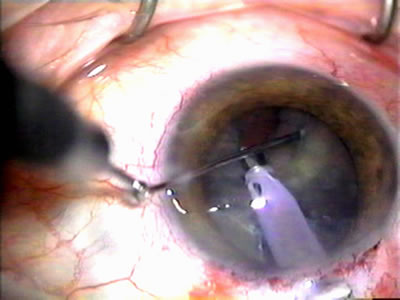

Fig. 1. The anatomic advantage of small incision cataract surgery for the glaucoma patient. A. Long-term bleb function with a large cataract incision is difficult to achieve with either ECCE-trabeculectomy or trabeculectomy followed later by ECCE. This bleb failed to form sufficiently when combined with large incision ECCE. The inflammation, bleeding, and long-term wound healing with stimulation of fibroblasts associated with this technique are more likely to cause bleb failure. In addition, the increased iris manipulation necessary to deliver the nucleus and subsequent iris repair adds to the long-term breakdown of the blood aqueous barrier. B and C. Two-site phacotrabeculectomy has the advantage of small incision cataract surgery combined with separate site trabeculectomy. The incision size is one third the size of the standard ECCE. The inflammation is less severe, and cataract wound healing is confined to the temporal area. Visual rehabilitation with phacoemulsification and foldable IOL is much faster. Phacoemulsification allows successful lens extraction even in the unfriendly environment of a smaller pupil compared with ECCE. The trabeculectomy is performed in an entirely different site, well away from the wound healing associated with temporal phacoemulsification. The likelihood of this filter functioning long-term is greater than with ECCE-trabeculectomy. D. The surgeon also has the option of single-site phacotrabeculectomy with foldable IOL. Both the lens extraction and trabeculectomy are performed through one small 3.5-mm limbal incision.